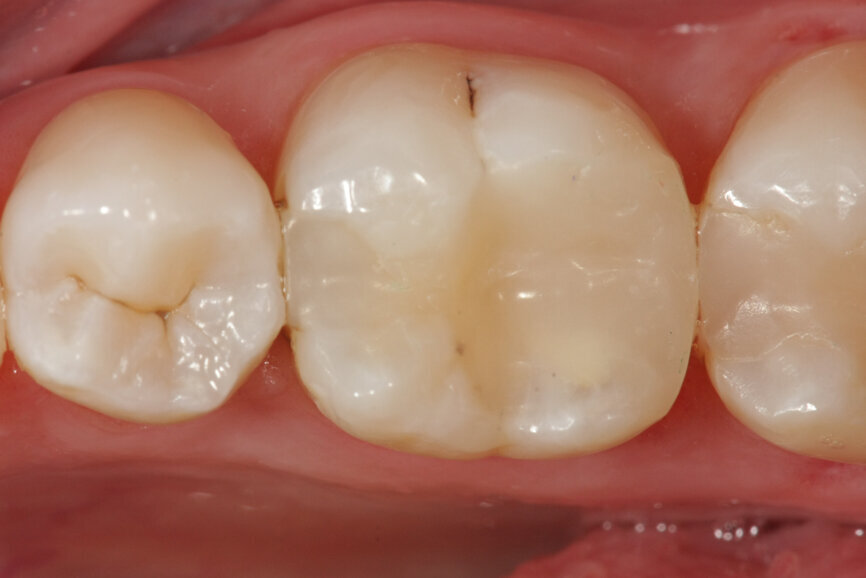

Vital pulp therapy has become more popular in recent years. Calcium hydroxide has been the most common material for pulp capping, but MTA has shown even better results in biocompatibility and outcome.[3] Cases with large carious pulp exposure can be treated successfully with partial pulpotomy and MTA as a capping agent, keeping teeth vital (Figs. 1a–e).

Fig. 1a: (a) Deep carious lesion. (b) Partial pulpotomy. (c) MTA application with the MAP System and PD MTA White. (d) Filling. (e) Post-op radiograph showing the pulp capping with MTA.

Fig. 1b: (a) Deep carious lesion. (b) Partial pulpotomy. (c) MTA application with the MAP System and PD MTA White. (d) Filling. (e) Post-op radiograph showing the pulp capping with MTA.

Fig. 1c: (a) Deep carious lesion. (b) Partial pulpotomy. (c) MTA application with the MAP System and PD MTA White. (d) Filling. (e) Post-op radiograph showing the pulp capping with MTA.

Fig. 1d: (a) Deep carious lesion. (b) Partial pulpotomy. (c) MTA application with the MAP System and PD MTA White. (d) Filling. (e) Post-op radiograph showing the pulp capping with MTA.

Fig. 1e: (a) Deep carious lesion. (b) Partial pulpotomy. (c) MTA application with the MAP System and PD MTA White. (d) Filling. (e) Post-op radiograph showing the pulp capping with MTA.